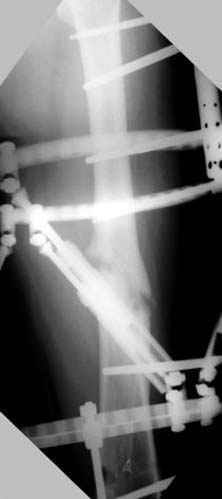

Несколько снимков из моей коллекции, чтобы разьяснить, почему мы до сих пор делаем различные варианты остеотомии.

На рисунке N1 предоперационный план лечения ложного сустава шейки бедра- линия ложного сустава, угол и направление введения импланта, клиновидная остеотомия в градусах и миллиметрах, второй снимок после коррекции, расчет, на сколько удлиняется конечность и размеры импланта;

N3 рисунок окончательный снимок, после операции моя рентгенограмма должен выглядеть примерно как эта картина. На N4 снимке клин перед удалением; N5 послеоперации 3 нед.; N6 окончательная рентгенограмма.

(доложен в Ст. Петербурге 2003 и в Москве 2004)

варус при проксимальном отделе 95 градусной пластиной.